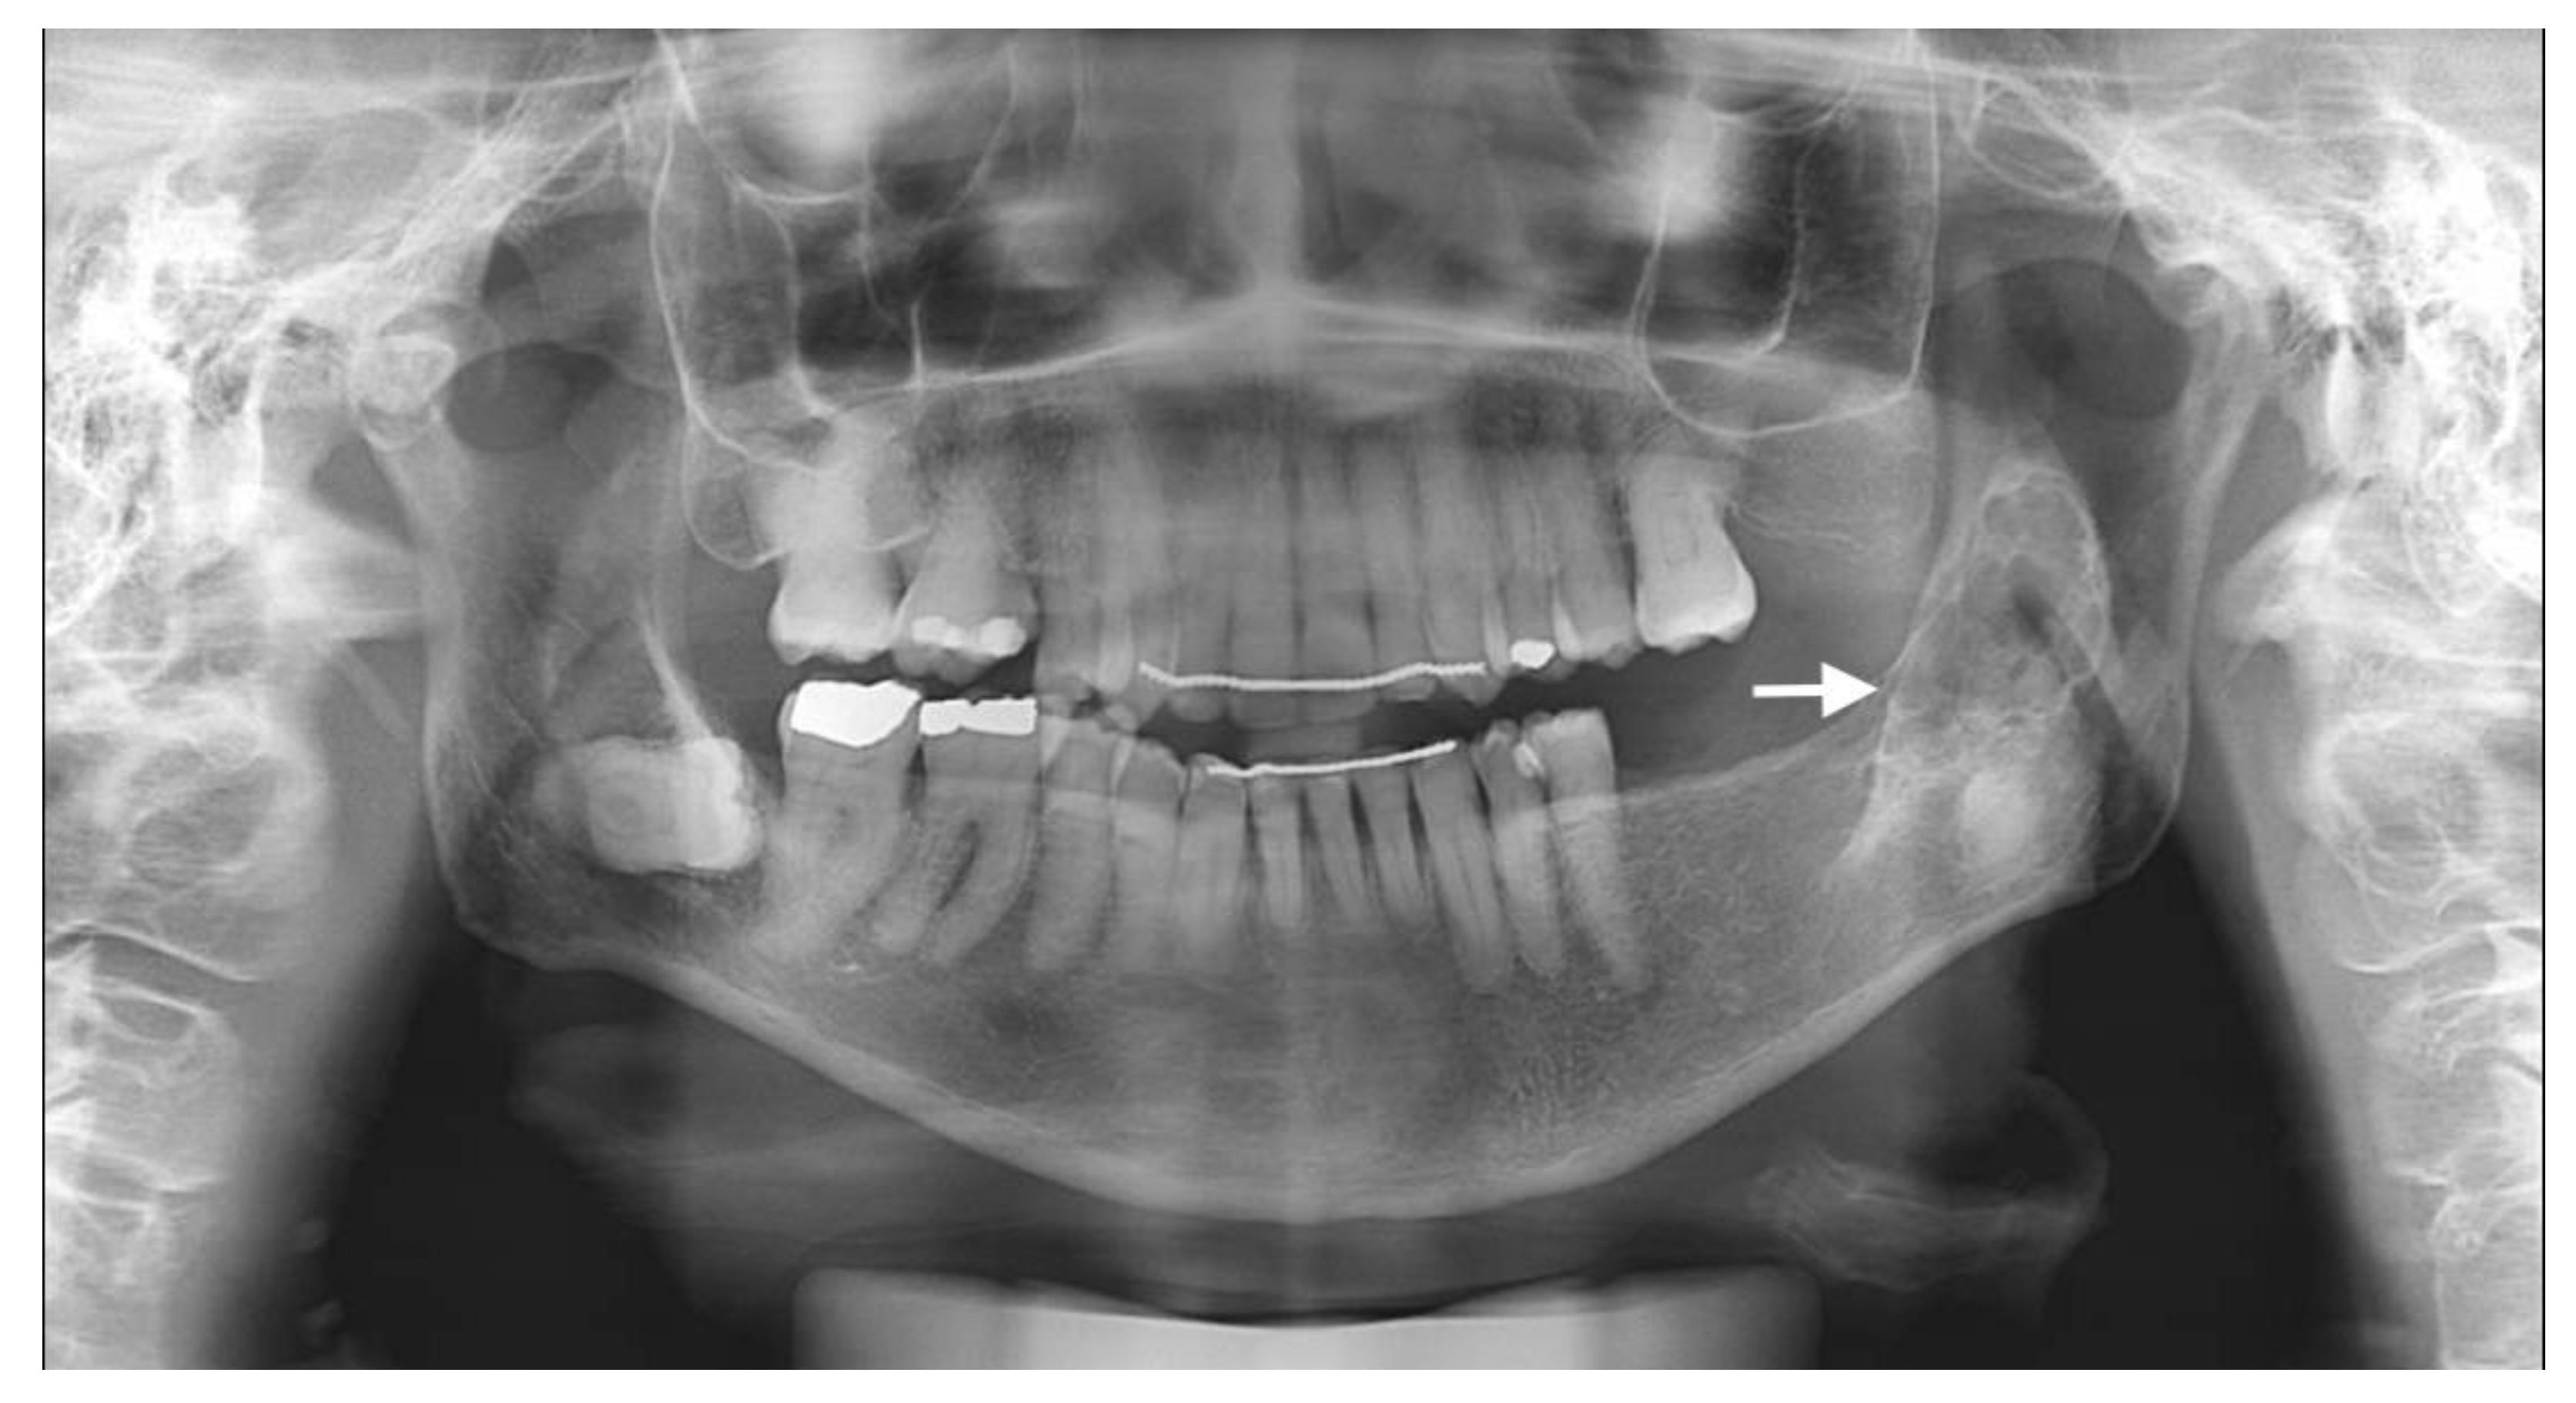

The usual diagnostic imaging study with a panoramic radiograph showed a well-defined mixed radiolucent–radiopaque lesion with peripheral enhancement in the left mandibular ramus occupying almost its entire thickness (Figure 1). Computed tomography performed with contrast was used to confirm the existence of a heterogeneously enhancing 3 cm long tumor with lobulated margins and bicortical expansion without bone perforation. Radiographically, there appeared to be an expansile cystic mass with areas of calcification and sclerotic borders. The mandibular lower border was intact (Figure 2A,B).

Figure 1.

Preoperative panoramic radiographic image. Radiolucency with many radiopaque spots described as driven snow appearance. No association with impacted teeth was seen (see arrow).

The clinical behavior is variable and usually presents as an intraosseous or central lesion, as in this case report. Extraosseous or peripheral lesions account for less than 5% of cases. The literature reports that the Pindborg tumor usually starts as painless intumescences that cause a slow bone expansion. It can show up at any age, but is more common in middle age, with a peak incidence in the fifth decade of life, and there is no sex predilection [6]. It usually develops in the posterior region of the mandible, as in our patient, with a mandibular to maxillary proportion of 3:1, and may present clinical and pathological similarities to other odontogenic lesions. It has been proposed that the Pindborg tumor stems from the stratum intermedium of the dental organ or from the dental lamina. The radiological aspects observed are variable and depend on the time of evolution of lesions and can present in different phases: only radiolucent lesions, radiolucent–radiopaque images as in our case, or only dense radiopaque areas. Pindborg tumors are mostly unilocular, but they can also be multilocular. Evidence of bone destruction is often present, and mottled densities caused by calcifications and ossification, described as a “driven snow appearance”, can occasionally be seen. In some cases, particularly in tumors of a relatively short period, the calcification is very small and may not be defined on radiographs. Nearly 50% of cases are associated with an unerupted tooth, which could not be proven in our patient because of a previous history of exodontia. When an unerupted tooth is incorporated with the tumor, the radiopacity is usually located near the tooth crown [3,4,7].